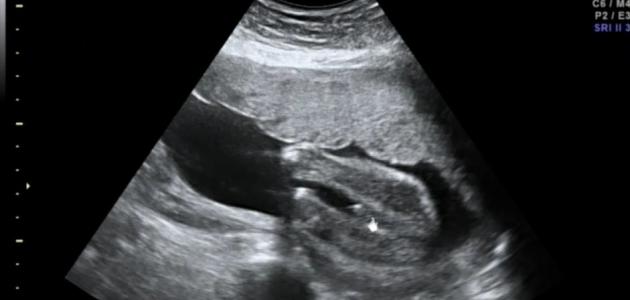

عادة ما يُستخدم فحص السونار أو التصوير بالموجات الصوتيّة (بالإنجليزيّة: Fetal Ultrasound) خلال فترة الحمل بهدف تصوير الجنين داخل الرحم (بالإنجليزيّة: Uterus)؛ حيثُ يتم من خلاله تقييم قلب الجنين، ورأسه، وعموده الفقري، وغيرها من أعضاء جسم الجنين، ويعتمد جهاز السونار في عمله على الموجات الصوتيّة المُطلقة عن طريق جهاز إلكتروني يُدعى بمُحوّل الطاقة (بالإنجليزيّة: Transducer)، ومن خلال انتقال الموجات الصوتيّة عبر طبقات الجلد، والعضلات، والسوائل، والعظام، ومن ثمّ انعكاسها؛ تنتج صورة إلكترونيّة للجنين على الجهاز، ويتم تطبيق مادة هُلاميّة على البطن عند إجراء الفحص بهدف تعزيز انتقال الموجات الصوتيّة وتسهيل حركة الجهاز على سطح البطن، وتجدر الإشارة إلى أنّ فحص السونار يُعدّ من الفحوصات الآمنة لتقييم الحمل؛ وذلك لعدم استخدام أي موجات إشعاعيّة خلال إجراء الفحص سواء كان عبر التصوير بالموجات الصوتيّة عن طريق المهبل (بالإنجليزيّة: Transvaginal Ultrasound)، أو التصوير بالموجات الصوتيّة عبر البطن (بالإنجليزيّة: Transabdominal Ultrasound).[١][٢]

في الحقيقة، هنالك ثلاثة أنواع مختلفة من فحص السونار أو الفحص بالموجات الصوتيّة: الفحص الاعتيادي أو الفحص ثنائي الأبعاد، وفحص دوبلر (بالإنجليزيّة: Doppler Ultrasound) الذي يقوم بقياس حركة الدم خلال الرحم وجسم الجنين، بالإضافة للفحص ثلاثيّ الأبعاد (بالإنجليزية: 3D Ultrasound) الذي يقوم بتزويد صورة مُطابقة للجنين،[١] وتجدر الإشارة إلى أنّ الفحص ثلاثيّ الأبعاد هو أكثر هذه الفحوصات دقة في تحديد جنس الجنين، وعادة ما يتم فحص السونار لتحديد جنس الجنين بعد الأسبوع الـ18 من الحمل؛ حيثُ إنّه قبل ذلك يكون البظر (بالإنجليزيّة: Clitoris) في جنين الأنثى يُساوي حجم العضو الذكري في الجنين الذكر، ممّا يؤدي إلى صعوبة التفريق بينهما، وتعتمد دقة النتيجة بشكل عام على العديد من العوامل: كعمر الجنين، ونوع الجهاز المُستخدم، والطبيب الذي يُجري الاختبار، بالإضافة لوضعيّة الجنين عند إجراء الفحص، ولذلك فمن الممكن ألّا تكون النتيجة صحيحة في العديد من الأحيان، وتكون الطريقة الوحيدة لتأكيد جنس الجنين بشكل كامل هي الانتظار حتّى الولادة، وفيما يلي بيان لبعض من العلامات والإشارات التي قد تظهر خلال فحص السونار ويتم من خلالها محاولة تقييم جنس الجنين:[٣][٤][٥]